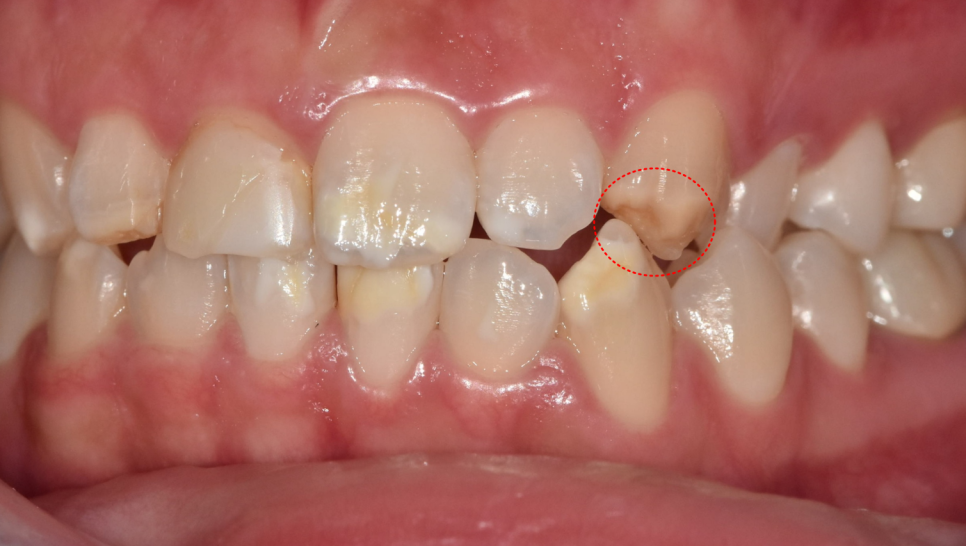

양측 송곳니를 보니,

반대편 치아와 물리는 부분이 너무 긴밀합니다.

쉽게 말하면, 위 치아가 아래 치아를 덮지 않고 씹는 면 끝과 끝이 물리더라고요.

이런 경우 라미네이트를 하면

깨질 가능성이 높습니다.

반면 지르코니아 크라운은 치아를 더 많이 깎는 대신

그만큼 보철이 더 두껍고 강도가 강합니다.

그래서 앞니 4개는 라미네이트로,

송곳니 3개는 지르코니아로 진행하기로 결정했습니다.